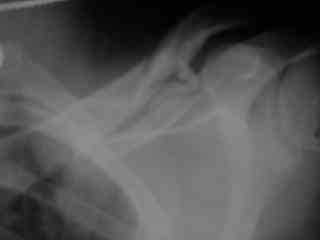

C> Postupil ko mne bolnoi s perelomom obeih kluchits, neznachitelny

C> pneumotorakx sleva.

Справа перелом практически поперечный, можно попробовать интрамедуллярно стержнем. Личного опыта правда не имею, у нас стандартом при оперативном лечении переломов ключицы является тот же остеосинтез пластиной. Но в литературе описана методика даже закрытого остеосинтеза - так, в порядке обсуждения.